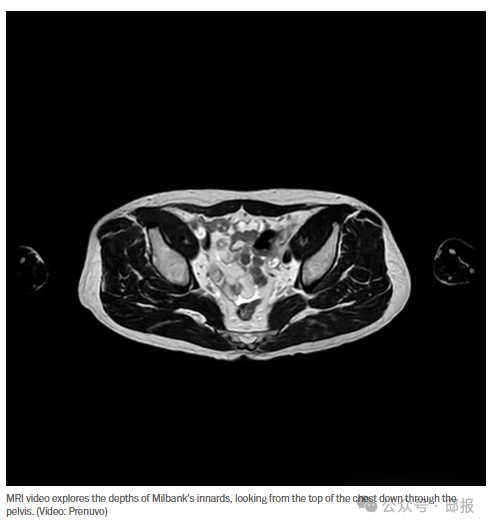

亲爱的读者,我没有什么需要对您隐瞒的,所以我在这篇专栏文章中附上了我的内脏照片。其他记者或许会高谈阔论透明度,但他们当中又有多少人向您展示过自己脾脏的视频呢?

接下来,我去了核磁共振舱,那是两台形似宇宙飞船的机器,位于相邻的房间里,灯光昏暗。我躺在平台上,技术人员给我戴上耳机(耳机里播放着默认的SPA音乐)和射频电极片,用来引导核磁共振扫描。然后他把我推进“宇宙飞船”里,接下来的半个小时里,我只能听从一个机械女声的指令,这个女声盖过了敲击声和砰砰声:“吸气。呼气。屏住呼吸。你可以再次呼吸了。”

所以我选择了价值1000美元的躯干扫描——虽然仍然很奢侈,但对更多人来说还是可以负担的。而且,它的性价比最高。“这是我们的强项,”莫迪说道,并指出在Prenuvo研究中检测到的22例癌症中,有17例位于胸部、腹部或盆腔。莫迪说,他们经常在这些部位发现一些癌症,而这些癌症往往要等到无法治愈才会被发现,比如“那些可怕的胰腺癌”。

除了书面报告外,还有一大堆扫描照片和视频,看起来像是炖牛膝和肋眼牛排的切片。其中有一段红色波浪线状的“肿瘤检测”序列;一个黑蓝色的旋转躯干;一段看起来像变形虫的“脂肪敏感序列”;各种显示器官、肌肉和骨骼溶解和重新出现的视频;以及一段显示我的胰腺像风向标一样旋转的视频。